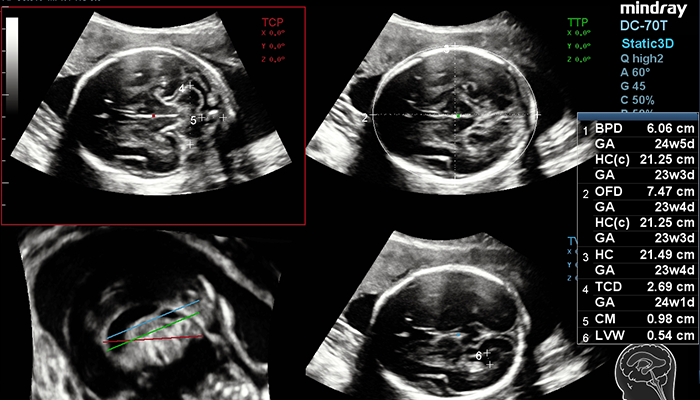

? Ak?ll? al?mla do?ruluk - Smart Planes CNS

Smart Planes CNS, tam otomatik ?al??an, tarama do?rulu?unu bΟΦyΟΦk ?l?ΟΦde art?ran, do?ru tan?, yΟΦksek verim ve daha az kullan?c? ba??ml?l??? sa?layan kullan?c? dostu bir ara?t?r. 3B fetal beyin hacim g?rΟΦntΟΦsΟΦne bir defa t?klad???n?zda, standart CNS tarama dΟΦzlemleri (MSP, TCP, TTP ve TVP) ve bir dizi ilgili anatomik ?l?ΟΦm (BPD, HC, OFD, TCD, CM ve LVW), yΟΦksek do?ruluk ile an?nda sunulur.

- Ak?ll? al?mla do?ruluk--- Smart Planes CNS

- Smart Planes CNS, tam otomatik ?al??an, tarama do?rulu?unu bΟΦyΟΦk ?l?ΟΦde art?ran, do?ru tan?, yΟΦksek verim ve daha az kullan?c? ba??ml?l??? sa?layan kullan?c? dostu bir ara?t?r. 3B fetal beyin hacim g?rΟΦntΟΦsΟΦne bir defa t?klad???n?zda, standart CNS tarama dΟΦzlemleri (MSP, TCP, TTP ve TVP) ve bir dizi ilgili anatomik ?l?ΟΦm (BPD, HC, OFD, TCD, CM ve LVW), yΟΦksek do?ruluk ile an?nda sunulur.